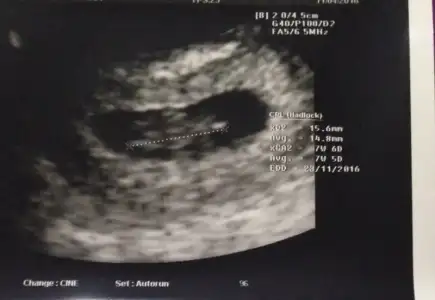

12+2 digeri 11+6 gittim doktor soylemedi 14+4 digeri 14+1 olduk 16 haftayi bekliyorum canim saglikla nasip etsin rabbim cumlemize insallahAynen öyle yaâsizin cinsiyet belli mi artık :)

Kızlar burda 7+5 ti yorum yapabilirmisinz :)